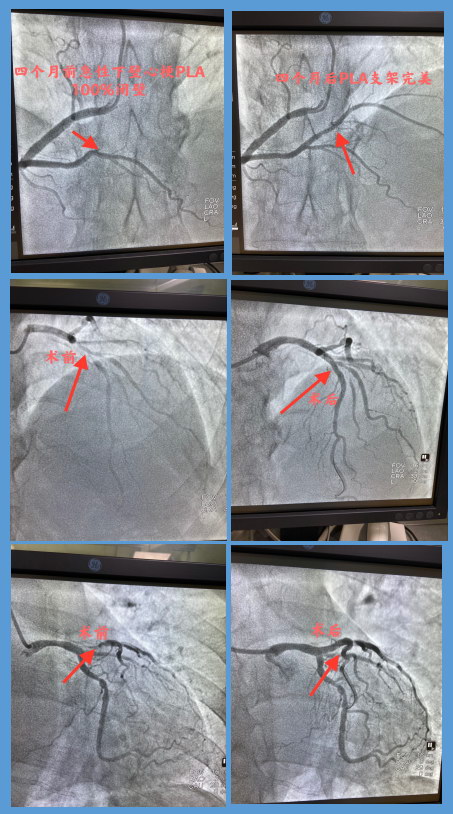

心血管内二科医生为他做心电图,结果显示下壁抬高型心肌梗死,病理性Q波已经形成。医生立即向于主任报告病情,并向患者及家属交代病情及冠脉造影相关注意事项,家属和患者同意造影手术。冠脉造影显示前降支近中段90%狭窄,D1可见95%狭窄,分叉病变严重钙化,回旋支中段可见70%左右狭窄,右冠PLA100%闭塞,右冠脉后侧支(PLA)为本次心梗的罪犯血管,经过于主任介入手术团队熟练的操作技术,于右冠PLA植入支架2枚,患者胸闷气短症状立即缓解,经过七天的治疗康复出院。出院前,于主任一再叮嘱患者要注意休息,避免劳累,戒烟戒酒,定时服药,监测血压,定期检查血脂、肝功、肾功能、血常规及凝血功能,3个月后要进行前降支分叉钙化病变治疗,以免再次出现胸闷气短等症状。

8月9日患者再次来到军工医院心血管内二科治疗前降支分叉钙化病变。复查造影显示右冠脉后侧支支架良好。